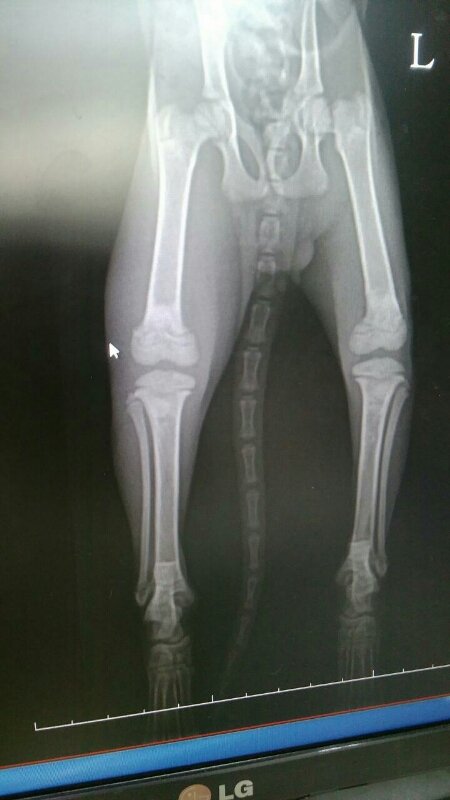

2개월령 0.86키로그램의 작디작은 아이가 오른쪽 다리 골절 왼쪽 고관절 골절 앞두다리도 부러졌다 붙고 있다고 합니다.

엑스레이 사진상으로도 한쪽다리가 많이 부어있습니다.

부러진지 3주정도 됐고 날카로운것에 찔린 상처들이 있다고 하십니다.

염증이 가득차서 많이 부어있고 열감이 느껴집니다.

다른 한쪽은 부러진지 일주일정도 되었다고 하십니다.